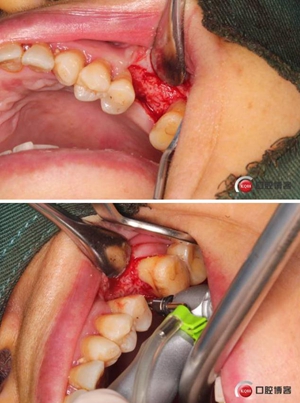

改良式外提升工具盒-外提 科貿(mào)嘉友收錄

大家好,我是梁老師的助理小依。由于梁老師每天手術(shù)檔期安排較滿,加上經(jīng)常出差講課,沒有時(shí)間整理病例 。為了方便大家更及時(shí)的了解梁老師最新手術(shù)動(dòng)態(tài),以后將由我為大家整理并推送梁老師最新經(jīng)典案例。案例文字旁白少,但圖片會(huì)盡量完整展示手術(shù)全過程,供大家學(xué)習(xí)參考。有任何問題,可以留言,梁老師會(huì)親自為大家解答。感謝大家對梁老師的支持和關(guān)注!

六個(gè)月之后